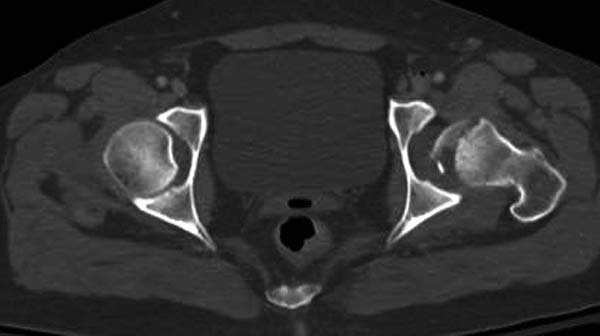

Женщина 28 лет, политравма.

По протоколу обследования больных с травмой сделаны все исследования и выставлен диагноз: разрыв печени и селезенки; множественные переломы ребер и лицевого черепа; стабильный перелом позвоночника, переломо-вывих головки левого бедра, перелом диафиза правого бедра, переломо-вывих правого тарана.

Имя     : 6 CT1.jpg

Тип     : image/jpg